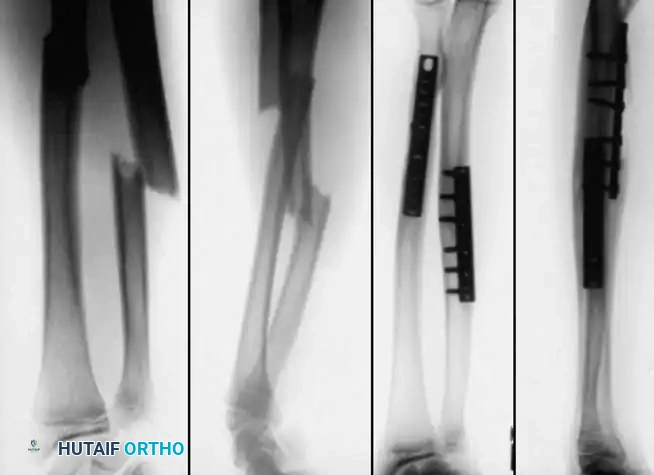

SURGICAL TECHNIQUES FOR DIAPHYSEAL FRACTURES

When operative intervention is mandated, the surgeon must choose between Elastic Stable Intramedullary Nailing (ESIN) and Plate Osteosynthesis.

1. Plate Osteosynthesis

Compression plating is highly effective, particularly in older adolescents with adult-type fracture patterns or in cases of malunion requiring osteotomy. Vainionpää et al. and Bhaskar and Roberts demonstrated excellent results with 3.5mm LC-DCP (Limited Contact Dynamic Compression Plates) or one-third tubular plates.

Surgical Warning: A compression plate must never cross an open physis, even in an older child nearing maturity, to prevent catastrophic growth arrest.

Technique Overview:

* Radius Approach: The volar Henry approach is preferred for middle and distal third fractures, utilizing the internervous plane between the brachioradialis (radial nerve) and flexor carpi radialis (median nerve). The dorsal Thompson approach can be used for proximal fractures.

* Ulna Approach: A direct subcutaneous approach along the subcutaneous border of the ulna.

* Fixation: Anatomical reduction is achieved. A minimum of three bicortical screws (six cortices) should be placed on each side of the fracture.

* Single Bone Plating: Bhaskar and Roberts noted that if plating the ulna alone restores acceptable alignment and stability to the radius, radial plating may be avoided to minimize surgical morbidity.

Image